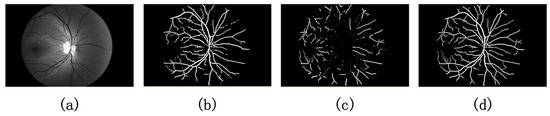

4.1. Comparison of Dual-Wavelength Retinal Image Segmentation Results